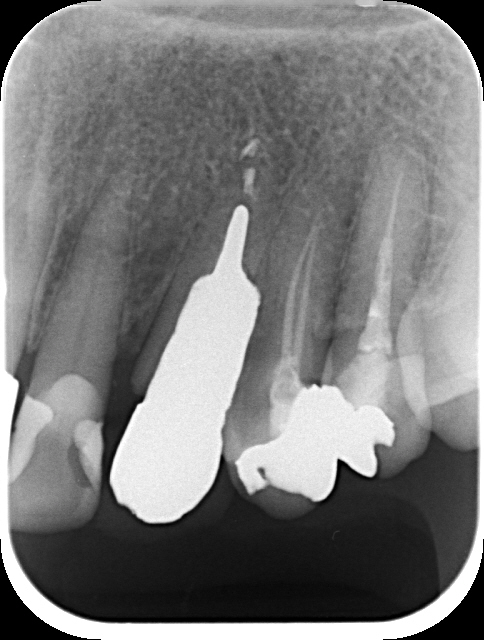

レントゲン写真を見ると、何度も脱離の度に作り直しているからか、このように太くて長い土台が装着されており、残存歯質はあまりない状態でした。

クラウンと土台は簡単に外れ、歯根をよく観察してみると、予想していた通り破折線が認められました。

この状態では、再度被せなおしたとしても、中長期的に維持するのは難しいことを患者さんに説明し、

抜歯してインプラント治療を行うことになりました。

抜歯後の歯槽骨は幅があまり無く、インプラントを埋入すると、術前の診断通り、インプラントの一部がこのように露出した状態になったので、人工骨と非吸収性メンブレンを使用した歯槽骨の造成(GBR)を行い縫合しました。

写真は、インプラント埋入+GBR 後です。